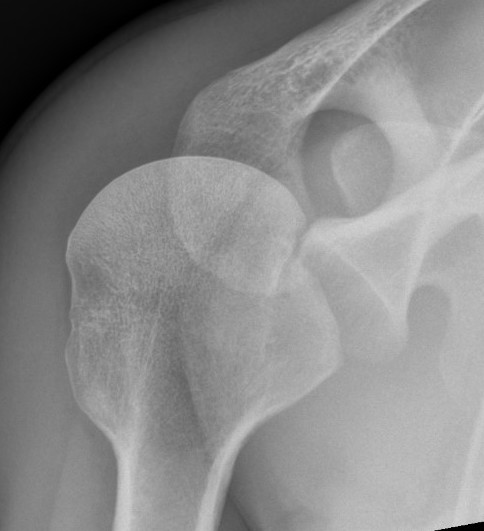

AP Xray

Abnormal overlap of humeral head on glenoid

Light-bulb sign - globular head secondary to internal rotation of the humeral head

Vacant Glenoid Cavity - > 6 mm space between humeral head and anterior rim of glenoid